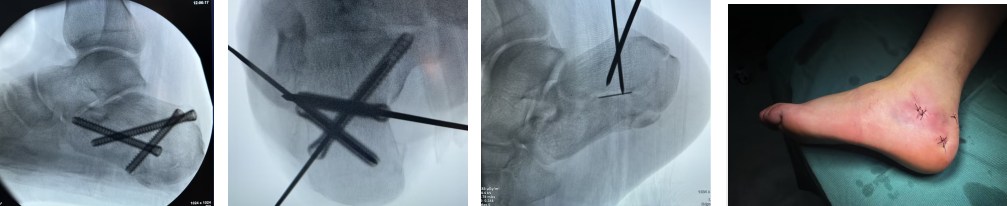

而创伤外一科的微创术式,恰好精准解决了这些痛点。医生无需切开大口子,仅用克氏针轻轻撬拨错位骨骼,配合体外撑开器精准调整位置,最后用埋头螺钉牢牢固定。整个过程精准轻柔,既能让骨头回归正确位置,恢复跟骨原本的高度与宽度,为后续康复打下坚实基础,更从根源上减少了对周围组织的损伤。

(术中)

创伤外一科团队充分理解王先生的担忧,详细讲解了微创技术的优势,还结合他的身体状况定制了专属手术方案。手术十分顺利,术后无感染等问题。